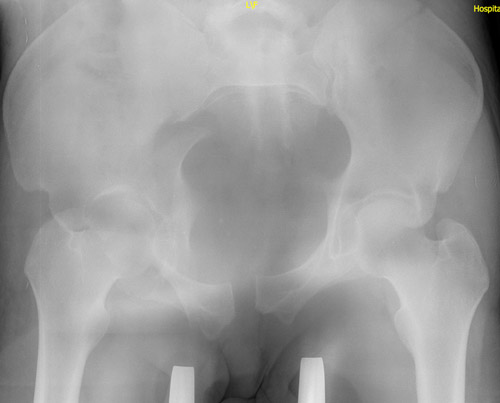

Emergency CT-scan with overthigthened binder

Emergency CT scan